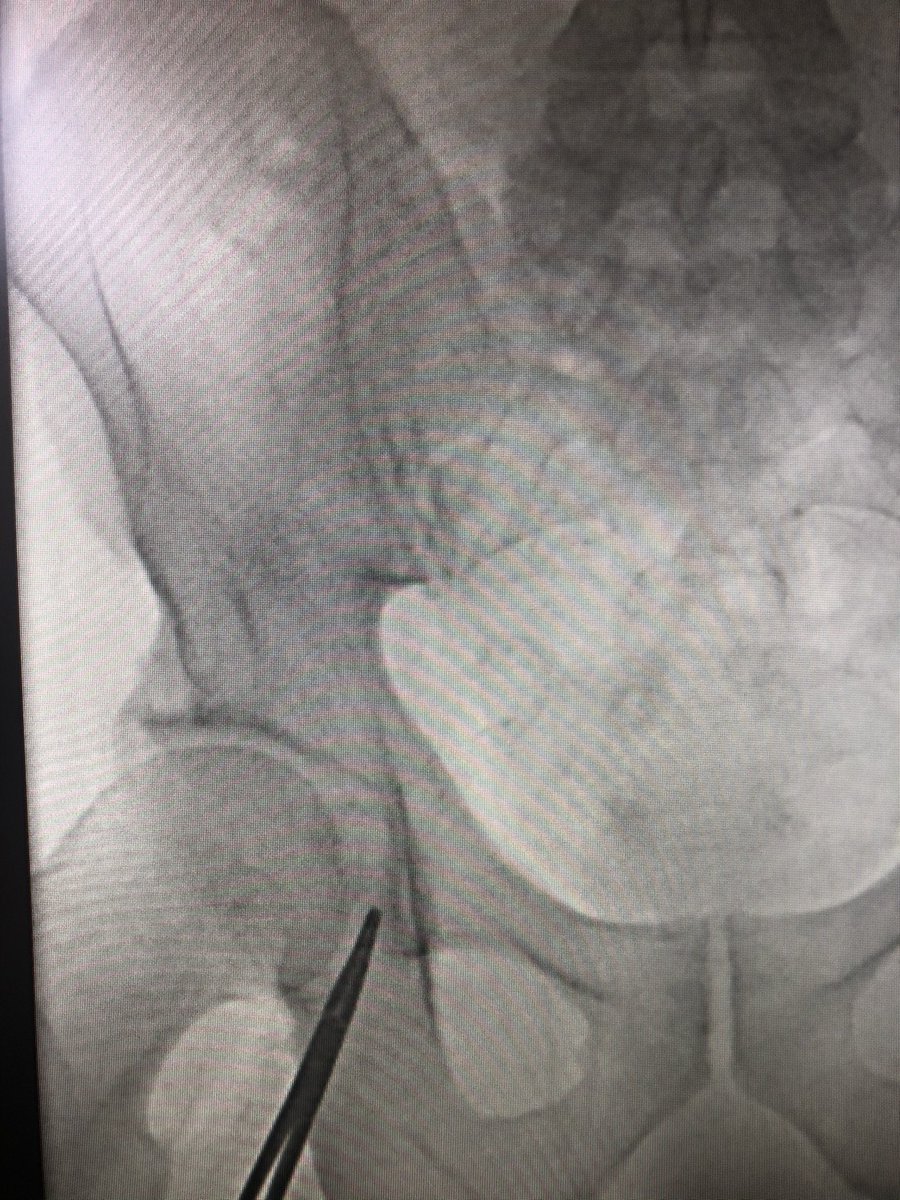

Step 2 - #UltrasoundAccess to identify common femoral and calcification (not shown) . Be above the femoral bifurcation. Insert micro puncture needle to access but not puncture the artery. Quick fluoro check to make sure puncture will be in #SafeZone. (Shown) #JointCathConference